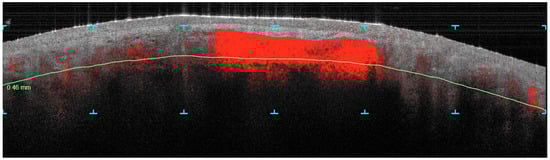

Figure 1.

Vertical image captured at the depth of 46 mm displays the pre-treatment condition with evident vascularization, particularly a uniform red vascular blotch in the middle third of the nose’s dorsum. The green line indicates the depth of the skin being analyzed, while the blue symbols mark the area of focus.

Figure 2.

Vertical image captured at the depth of 46 mm. It shows the disappearance of the vascular feature in the post-treatment phase, underscoring the effectiveness of the combined CO2 and dye laser therapy in reducing vascular abnormalities and improving the skin texture and structure in rhinophyma. The green line indicates the depth of the skin being analyzed, while the blue symbols mark the area of focus.